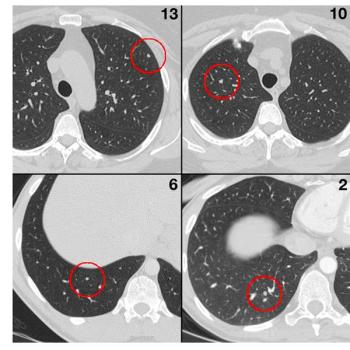

Radiologists tend to focus on certain areas of lung CT images, which could result in missed nodules.